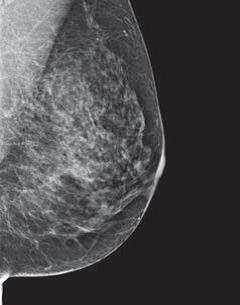

Categorías de densidad de los senos

Los radiólogos utilizan el sistema BI-RADS para clasificar la densidad mamaria en 4 categorías que van desde tejido adiposo casi en su totalidad hasta tejido extremadamente denso con muy poca grasa:

Algunos informes de mamografía que se envían a las mujeres indican la densidad mamaria. Su médico también puede decirle si su mamograma muestra que usted tiene senos densos.

¿Por qué es importante la densidad de los senos?

Las mujeres con tejido mamario denso parecen tener un riesgo ligeramente mayor de padecer cáncer de seno que las mujeres con tejido mamario menos denso. Por el momento, no está claro por qué el tejido mamario denso está relacionado con el riesgo de padecer cáncer de seno.

Sabemos que el tejido mamario denso dificulta que los radiólogos detecten el cáncer. En los mamogramas, el tejido mamario denso se ve blanco. Las masas o tumores de los senos también lucen de color blanco, por lo que la densidad del tejido puede ocultar algunos tumores. Por el contrario, tejido graso se ve casi negro. Sobre un fondo negro es más fácil identificar un tumor que se ve blanco. Por esta razón, los mamogramas pueden ser menos precisos en mujeres con senos densos.